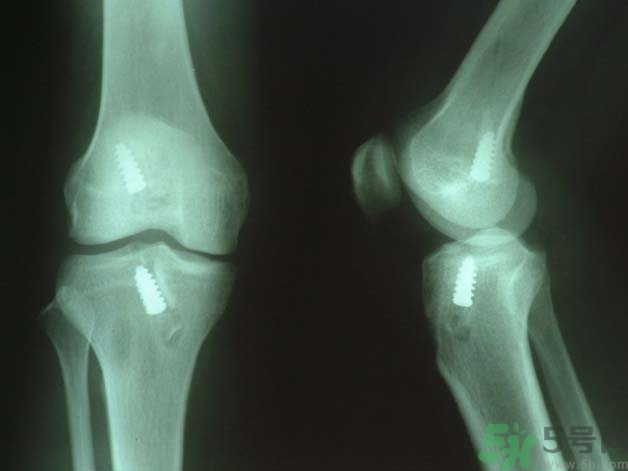

原則上應(yīng)行手術(shù)治療如韌帶斷裂,可直接縫合;如骨附著處撕脫,可用鋼絲貫穿法固定或直接縫合于骨膜及軟組織上。如有撕脫骨片,則用鋼絲或螺絲釘固定。如合并半月軟骨損傷,應(yīng)予以切除。合并前膝交叉韌帶損傷者,應(yīng)先修補(bǔ)。術(shù)后石膏固定4—6周。

前交叉韌帶合并脛骨棘撕脫骨折者,可用膝過(guò)伸和后推脛骨使之復(fù)位,用長(zhǎng)腿石膏固定4—6周。對(duì)于未能復(fù)位者,應(yīng)及時(shí)手術(shù)修補(bǔ)。將骨折片用鋼絲固定。單純韌帶斷裂者,用石膏固定。對(duì)陳舊性損傷,以保守治療為主,經(jīng)鍛煉后,關(guān)節(jié)仍不穩(wěn)定,亦可考慮手術(shù)修補(bǔ)。后交叉韌帶可不修補(bǔ)。